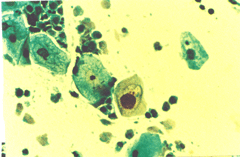

Περιστατικό ασθενούς που παρακολουθείται στο ιατρείο μας από το 1993, τότε ηλικίας 37 ετών, αρχικά λόγω ασυμπατωματικού κυτταρολογικά εμμένοντας έρπητος τραχήλου της μήτρας. Το γεγονός αυτό μας οδήγησε στην διερεύνηση της περιπτώσεως. Η ασθενής επασχε από A.I.D.S.

Είχαμε την ευκαρία να παρακολουθήσουμε ανά 6μηνο γυναικολογικά, κολποσκοιπικά και κυτταρολογικά την γυναίκα από το 1993 μεχρι και το 2008. Από τις εξετασεις αυτές, παρουσιάζουμε χαρακτηριστικές κυτταρολογικές εικόνες . Όι παρακάτω κυτταρολογικές εικονες προέρχονται από την 2η κατά σειρά εξέταση της ασθενούς το 1993. Οι κυτταρολογικές αλλοιώσεις ερπητος συνεχίζουν να υφίστανται.

Ταση γιγαντιοκυττάρωσης όλων των επιθηλιακώ στοιβάδων, κοιλοκυττάρωση, διογκωμένοι υπερχρωματικοί και ανισομεγέθεις πυρήνες , με διάλυση δομής χρωματίνης, συχνά διογκωμενοι πυρήνες με εικόνα φαινομένου ΄΄θολού γυαλιού΄΄